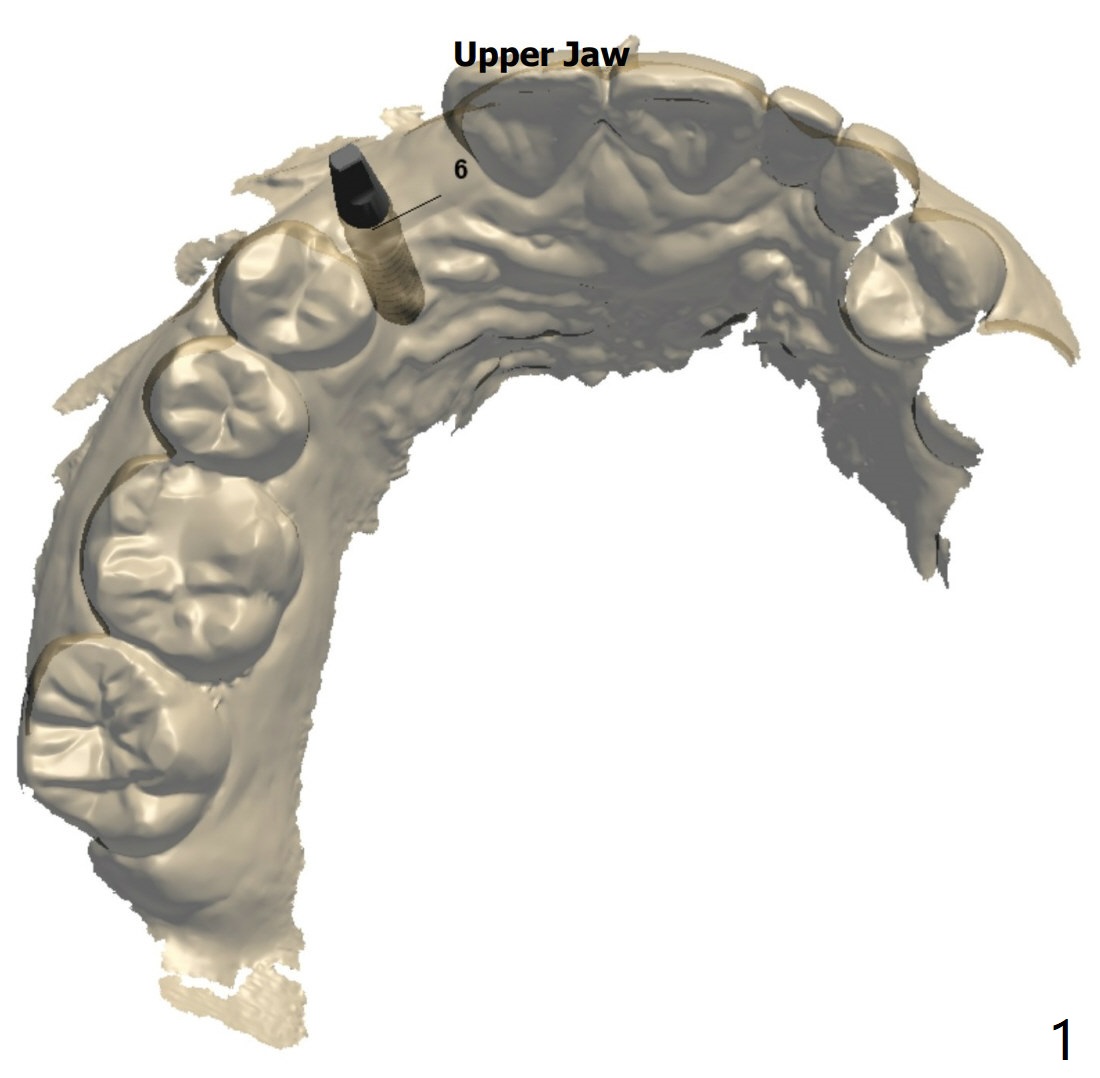

第二次植入

6号牙植体取出植骨5.5月,需要切开去除带钛不可吸收膜和两个固定钉,抽血一管